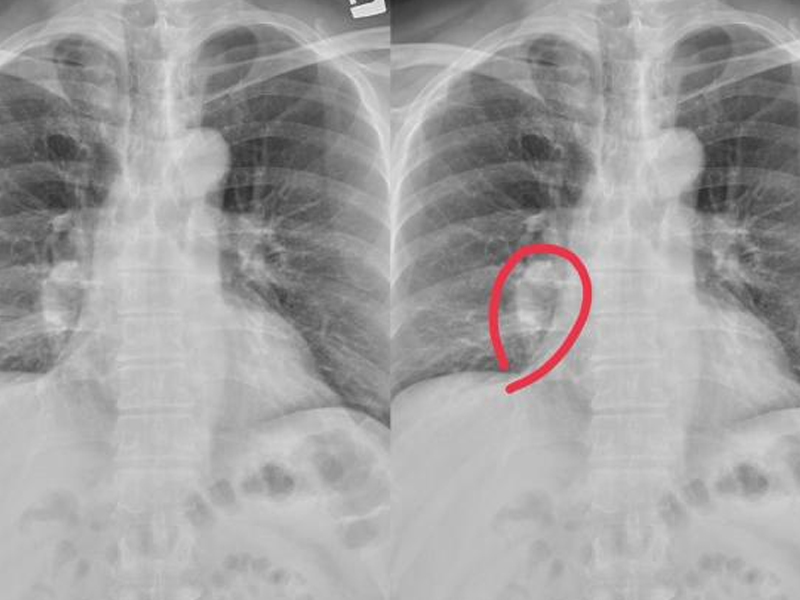

| 膽結石是一種常見的健康問題,特別是在女性中更為普遍。儘管許多患者終其一生都不會出現症狀,但一旦膽結石引發膽囊或膽管發炎,就會帶來劇烈的疼痛及其他嚴重的健康問題。本文將詳細介紹膽結石的成因、不同類型、可能出現的症狀以及目前可用的治療方法。 膽結石的成因 當我們進食時,膽囊會開始收縮並將儲存的膽汁運送到十二指腸幫助消化。然而,由於體質、膽囊功能問題或空腹太久等原因,某些人的膽囊長時間未受刺激,導致膽汁濃縮並最終形成膽結石。此外,女性罹患膽結石的機率是男性的兩倍,這與女性荷爾蒙有關,特別是懷孕次數較多、使用口服避孕藥或正在接受荷爾蒙治療的女性更容易患病。 膽結石的種類 膽結石根據其成分可分為三種主要類型:膽固醇結石(cholesterol gallstones)、黑色素結石(black pigment stones)和棕色素結石(brown pigment stones)。大約 80% 的膽結石屬於膽固醇結石,這些結石主要由膽固醇、膽紅素和鈣鹽組成,顏色偏黃且質地較軟。隨著飲食習慣的西化,人們攝入更多高油脂、高熱量的食物,血中的膽固醇水平升高,進一步增加了膽固醇結石的發生率。 黑色素結石主要由膽紅素和鈣組成,通常與溶血性疾病相關;而棕色素結石則多由膽道感染引起,過去與寄生蟲有關,但在現代社會已較少見。 症狀與診斷 大多數膽結石患者終身不會出現任何症狀,往往是在進行健康檢查時意外發現膽結石的存在。然而,若膽結石引發膽囊或膽管發炎,患者可能會感到右上腹部劇烈疼痛,這種情況稱為膽絞痛,通常在食用油膩食物後發生。疼痛還可能擴散至胸部或右肩胛骨,並且無論如何改變姿勢都無法減輕。 醫生通過超音波影像特徵可以大致判斷膽結石的屬性。如果膽結石造成膽囊發炎,醫師按壓該部位時,病人吸氣會導致疼痛加劇,這是牟菲氏病徵(Murphy’s sign)的一個表現。嚴重的情況下,膽結石可能導致膽囊破裂、腹膜炎甚至敗血症。 治療方法 膽結石的治療需考慮患者的症狀、手術風險、結石的種類與數量等因素。對於無症狀的膽結石患者,通常只需要定期追蹤觀察,而不需要立即處理。但如果膽結石引發膽囊或膽管發炎,手術摘除膽囊是最有效的治療方式,可以預防膽結石復發及併發症的發生。 微創腹腔鏡切除膽囊成為主流治療方法,因其具有住院時間短、組織傷害少等優點。手術過程中,醫師只需在腹部打 3 至 4 個小洞即可完成膽囊摘除,相比傳統手術,這種方法顯著降低了患者的疼痛感和恢復時間。 對於無法進行手術的患者,醫師可能會選擇抗生素治療來控制炎症,或者進行經皮穿肝膽囊攝影引流術(percutaneous transhepatic gallbladder drainage, PTGBD),先將膽汁引流以緩解症狀,再擇期進行手術。若膽結石從膽囊掉出並卡住總膽管,內視鏡逆行性膽胰道攝影(endoscopic retrograde cholangiopancreatography, ERCP)則是診斷與治療的重要手段。 |